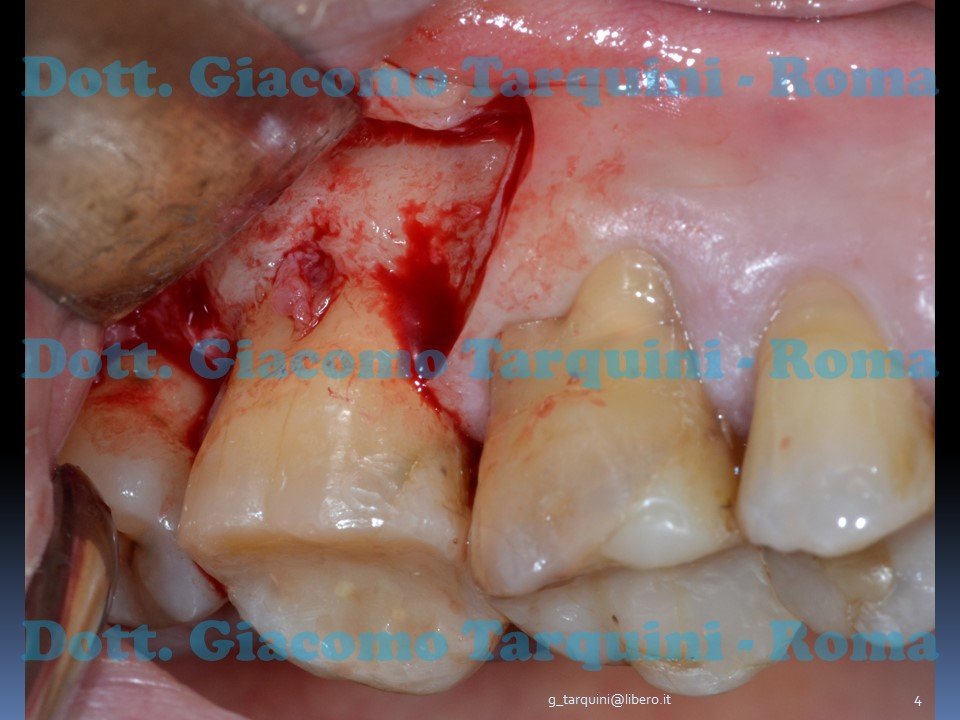

GBR Con Membrana Intenzionalmente Esposta